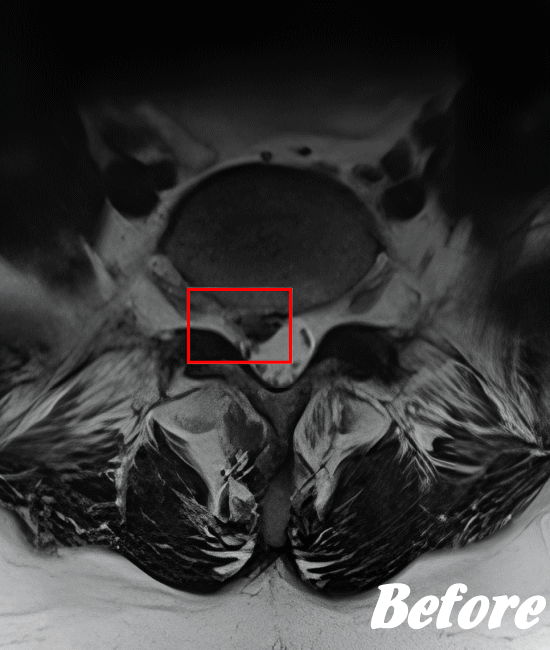

| 施術前(MRI) | 施術後(MRI) |

![]() |